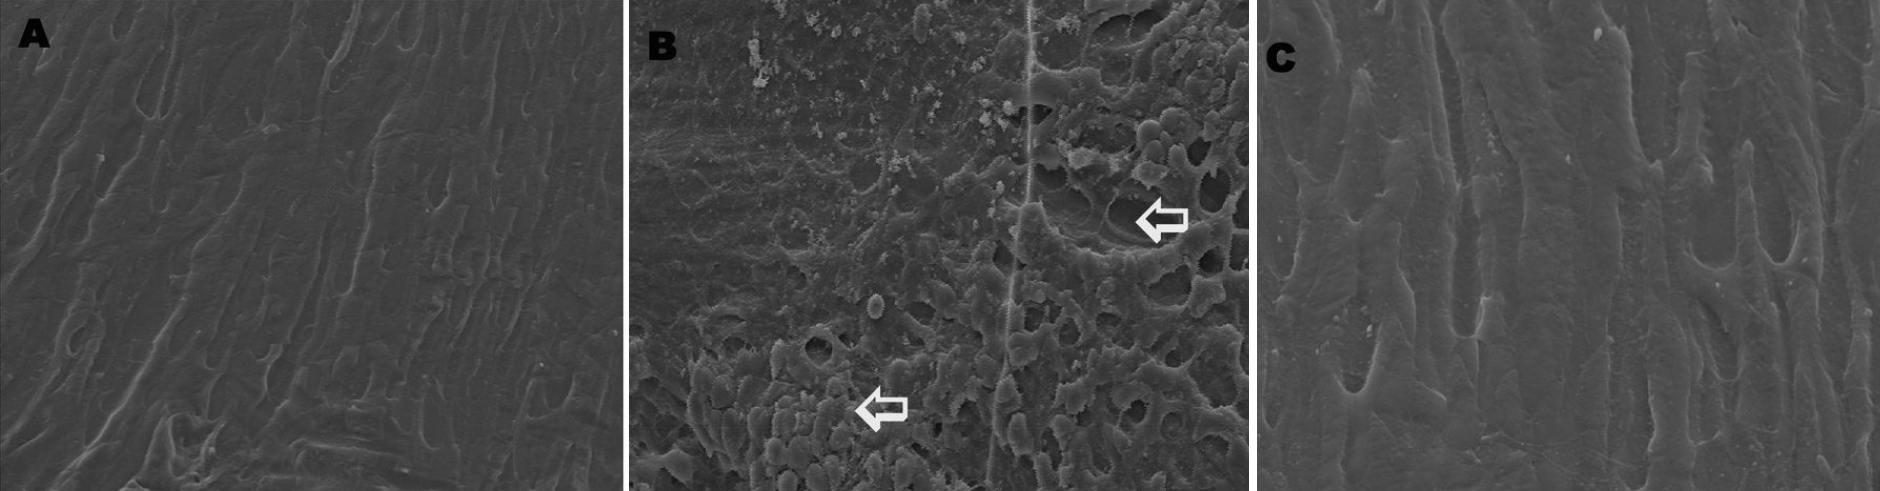

Figure 6. Scanning electron microscopic

changes. A: Control, B: Selenite induced, C:

Selenite + FVN treated. Dissected lenses were fixed in 3%

glutaraldehyde in 0.1 M phosphate buffer at 4 °C. After fixation

the lenses were dehydrated in graded acetone series and critical point

dried. The lenses were then coated with gold and used for the SEM study

under a Philips scanning electron microscope 501(B) at 50 kV.

Magnification – 2,000×. Arrows indicates abnormal fiber structure and

numerous spherical bodies in lens.